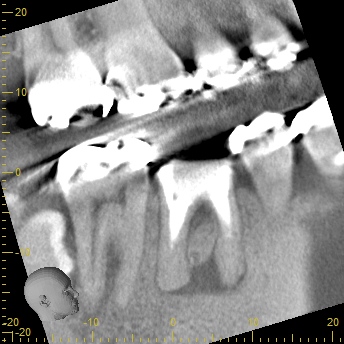

次の画像をご覧ください。これは、CTとレントゲンで同じ患部を撮影した画像です。

左の画像がCT、右がレントゲンで撮影したものです。

左の写真の赤丸で囲んだところは黒い影が映っています。これは「炎症」を示しています。一方、右の写真には黒い影はありません。つまり、レントゲンだけを使って診断すると、この炎症には気付かないということです。放置している間にこの炎症は悪化し、抜歯となってしまうかもしれません。

CTの鮮明な影像によって、正確な診断が可能になります。